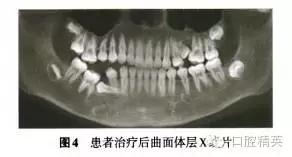

診斷:安氏Ⅲ類亞類錯(cuò)牙合畸形,5V、5V阻生。治療方案:①拔除V,V,清理V囊腔;②牽引5至正常牙列;③試牽引5,不排除牽引失敗的可能;④使用種植體支抗防止鄰牙壓低和對(duì)牙合牙伸長(zhǎng);⑤糾正右側(cè)后牙開牙合,若654粘連導(dǎo)致正畸治療無(wú)效,則需調(diào)整治療方案。拔除埋伏乳磨牙時(shí),錐形束CT確認(rèn)下頜神經(jīng)管位于阻生V根分叉下方(圖3),5牙根位于43舌側(cè)。手術(shù)順利拔除埋伏阻生的V、V,8個(gè)月后曲面體層x線片示牙槽骨愈合良好,可見4顆第三磨牙牙胚(圖4)。但患者家長(zhǎng)放棄牽引治療。